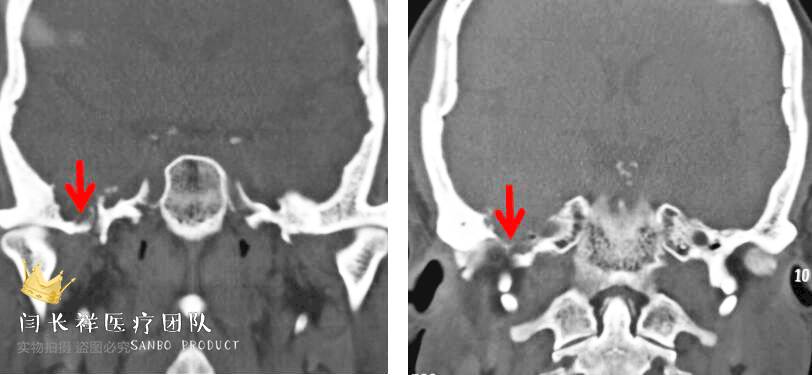

中颅窝-颞下窝占位

术前冠位CT骨窗像示右侧中颅窝底骨质被肿瘤侵蚀破坏。